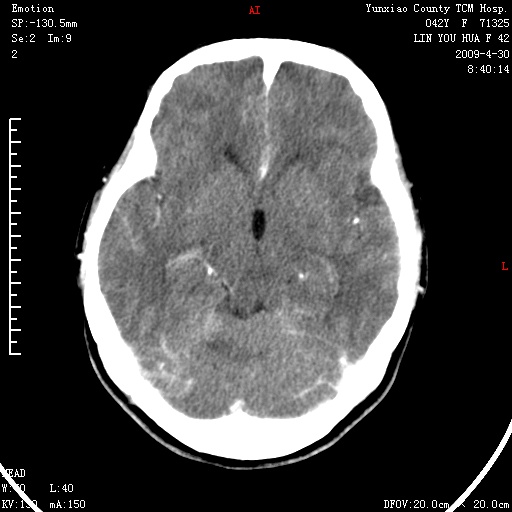

右侧桥小脑角区肿瘤,高密度囊变有显著强化,骨窗见内听道显著扩大,考虑听神经瘤可能性大

1)右侧听神经瘤。2)阻塞性脑积水。

内听道扩大,支持考虑听神经瘤可能性大。